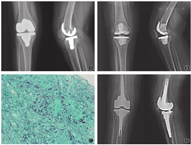

入院检查:跛行步态,右膝关节轻度红肿,前正中纵向15 cm手术切口愈合良好,切口远端下方可见0.5 cm×0.5 cm窦道,有少量浑浊、淡黄色液体渗出。关节皮肤温度较对侧略升高,关节屈伸活动度0°-30°。右下肢感觉、运动、反射均正常。X线片未见假体明确松动,位置良好(图1A)。实验室检查:红细胞沉降率为12 mm/1 h,C反应蛋白为1.06 mg/L,降钙素原<0.02 ng/ml;G试验、GM试验、冷凝集试验均阴性;结核感染T细胞检测:ESAT-6为14,CFP-10为4。关节穿刺获得5 ml浓稠血性关节液,细菌培养为阴性。

手术采用一期旷置二期翻修的方法。首先行右膝关节旷置术。沿原手术切口逐层进入膝关节腔,见少量血性关节液,留取标本。窦道与膝关节腔相通,窦道周围有少量坏死组织,未见干酪样坏死组织。彻底清除坏死失活组织和关节内粘连的瘢痕组织,检查膝关节假体固定牢靠、无松动。去除骨水泥后将假体与股骨、胫骨分离,股骨后方和胫骨下方可见少量灰色黏稠液体和质脆软组织,留取标本后彻底清除坏死失活组织和残余骨水泥。碘伏刷洗浸泡术区,用抗生素骨水泥塑形为股骨远端和胫骨近端占位器并分别置入(图1B)。术后连续3 d给予万古霉素(1 g/12 h静脉输液)及抗凝等对症处理。术中标本细菌培养阴性。病理检查结果:大量坏死组织,肉芽肿性炎,多核巨细胞结节,结核杆菌DNA检测阴性,抗酸染色、糖原染色、六胺银染色均为阴性(图1C)。术后第3天高通量测序报告病原微生物为贝纳柯克斯体,给予多西环素200 mg/d联合羟氯喹600 mg/d治疗。手术切口愈合情况良好,术后2周拆线,术后10周术侧皮肤温度恢复正常。

旷置术后4个月,患者术侧膝关节皮肤温度正常、略肿胀,手术切口愈合良好,各项炎症指标正常。再次入院行二期翻修术。沿原手术切口逐层进入膝关节腔,关节腔内有少量清亮关节液,留取标本。清除骨水泥占位器和周围瘢痕组织,未见明显坏死或感染组织。采用Vanguard®360全膝关节翻修系统(Zimmer Biomet,美国),分别于股骨远端及后髁骨缺损部加用金属垫块,股骨、胫骨侧使用髓腔延长杆(图1D)。术中标本培养结果为阴性。术后继续给予多西环素和羟氯喹治疗方案至术后2年,并嘱患者定期门诊复查。随访至术后6个月,患者右下肢股四头肌、腘绳肌肌力均5级,右膝关节伸屈活动度0°-100°。膝关节切口愈合良好,局部皮温正常。步态恢复正常,行走及上下楼梯无须辅助。